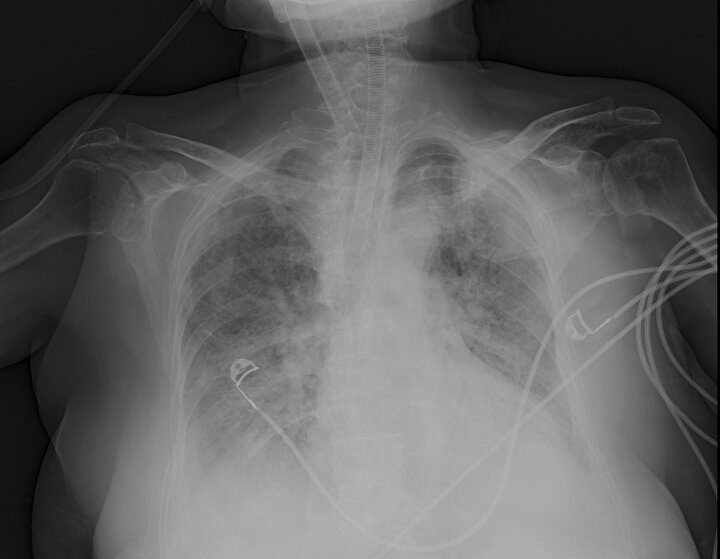

Ankara Şehir Hastanesinde koronavirüs tedavisi gören hastalara ait akciğer görüntüleri incelendi. Görüntülerde, hastalığın ne kadar hızlı ilerlediği ve akciğerleri nasıl tuttuğu ortaya çıktı.

Prof. Dr. Karalezli, koronavirüs tedavisi gören hastalara ait akciğer görüntülerinden hastalığın yol açtığı tahribatı ve hastalar üzerindeki etkileri anlattı.

Normal akciğer görüntüleri ile koronavirüs hastalarının akciğer görüntüleri arasında ciddi farklar bulunduğunu belirten Karalezli, şu bilgileri verdi:

"İnsanların aradaki farkları anlamaları için her iki akciğer görüntülerine de yer verdim. Görüntülerdeki beyazlıklar akciğerdeki tutulumu gösteren görüntüler ne yazık ki. Bu hastalar yoğun bakım hastaları. Filmler birbirine az çok benzeyen şekilde. Altta yatan hastalığı olanlarda ise daha kötü seyrediyor."